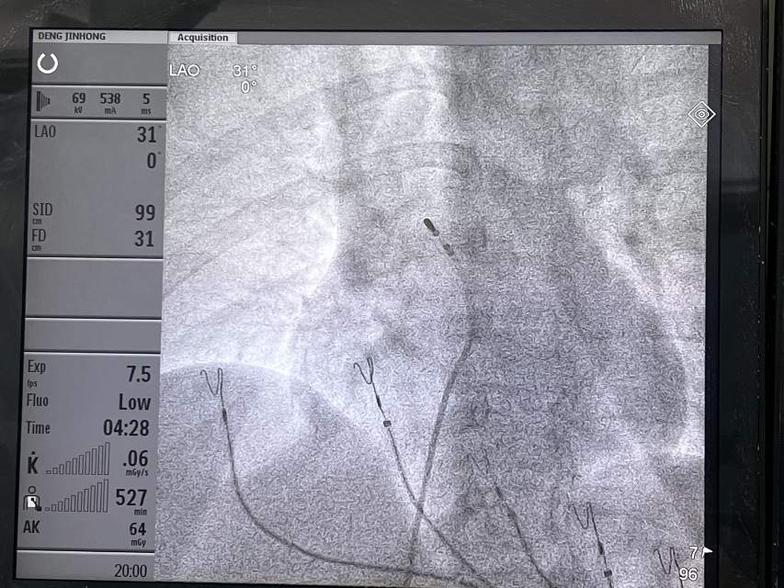

室早(室性期前收缩,RVOT来源)射频消融术

4.送入标测消融电极至右室流出道

5.标测最早心室激动点

6.消融前后心电图对比,消融过程中室早即消失。